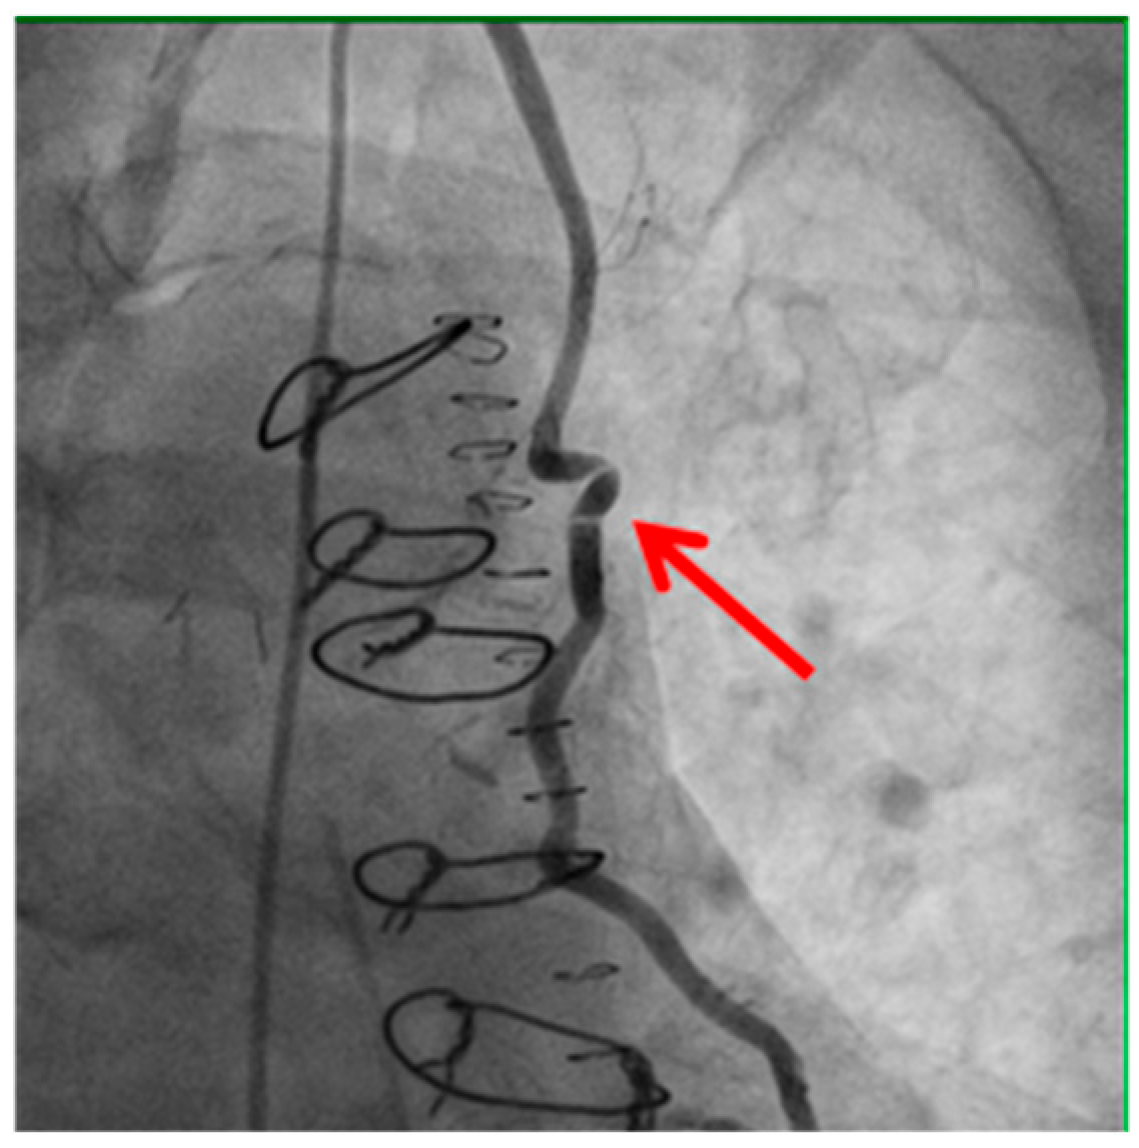

Technical issues remain a principal cause of PMI, with early graft thrombosis or occlusion being leading indications for uCAG (Figure 1, Figure 2, Figure 3 and Figure 4 illustrate typical technical causes, including proximal anastomotic stenosis, kinking, distal anastomotic stenosis, and misplaced anastomoses). Notable contributors include anastomotic stenosis, kinking, overstretching of grafts, and temporary graft spasm [13,21]. Prueßer et al. demonstrated that 30% of PMI cases detected via CAG were graft-related failures [13]. In this context, uCAG often reveals technical failures immediately post-surgery, providing the advantage of guiding targeted percutaneous coronary intervention or revascularization. Graft spasm, which can be relieved by nitrates, may also lead to acute ischemia. It refers to the temporary constriction of the bypass graft, reducing blood flow to the myocardium. This condition can be caused by various factors, including surgical trauma, inflammation, or the release of vasoactive substances [21].

Distal anastomotic stenosis (shown by the red arrow) observed on postoperative angiography. This finding underscores the potential for technical issues at the distal anastomosis site, which may require percutaneous intervention or revision surgery.

Figure 3. Stenosis of distal anastomosis.